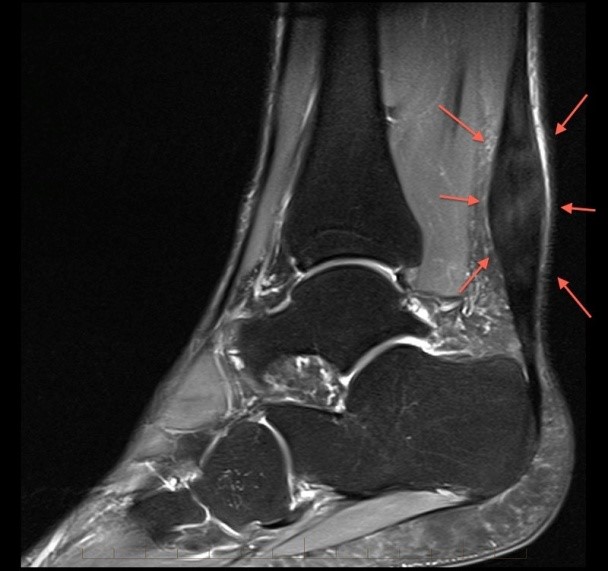

Ορισμός/Περιγραφή Η τενοντοπάθεια είναι η πιο κοινή διαταραχή του τένοντα, χαρακτηρίζεται κλινικά από τον πόνο , τη δυσλειτουργία και ιστοπαθολογικά από τον εκφυλισμό του τένοντα. Είναι κοινή στον αθλητισμό και...